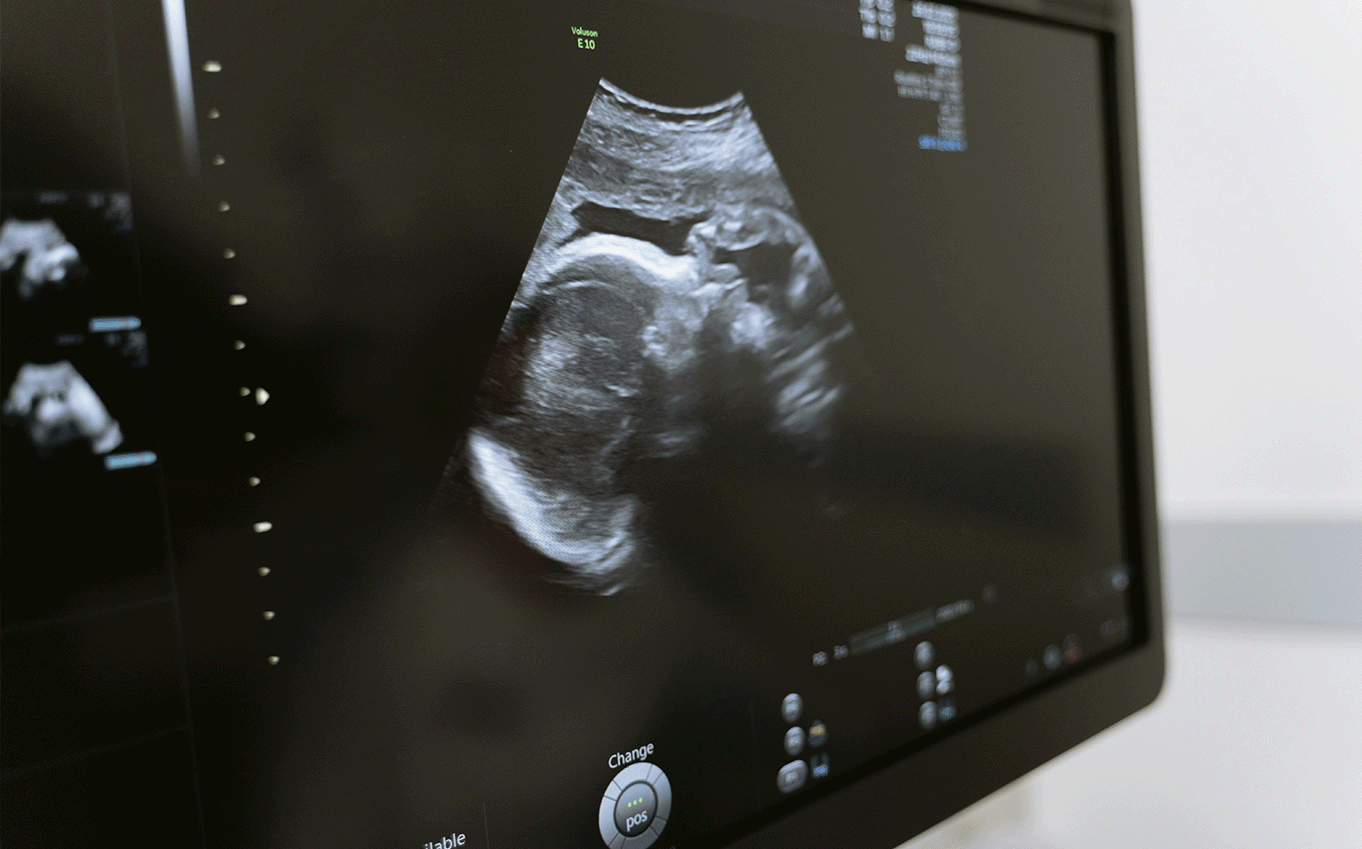

¿Cómo afectará la LMC al desarrollo del feto?

Debemos tener en cuenta que la LMC no altera el curso del embarazo, ni el embarazo altera el curso de la LMC. Sin embargo, los ITC deben evitarse durante el embarazo, especialmente en el primer trimestre. Pudiendo positivizar BCR-ABL e incluso desencadenar una progresión de la enfermedad.